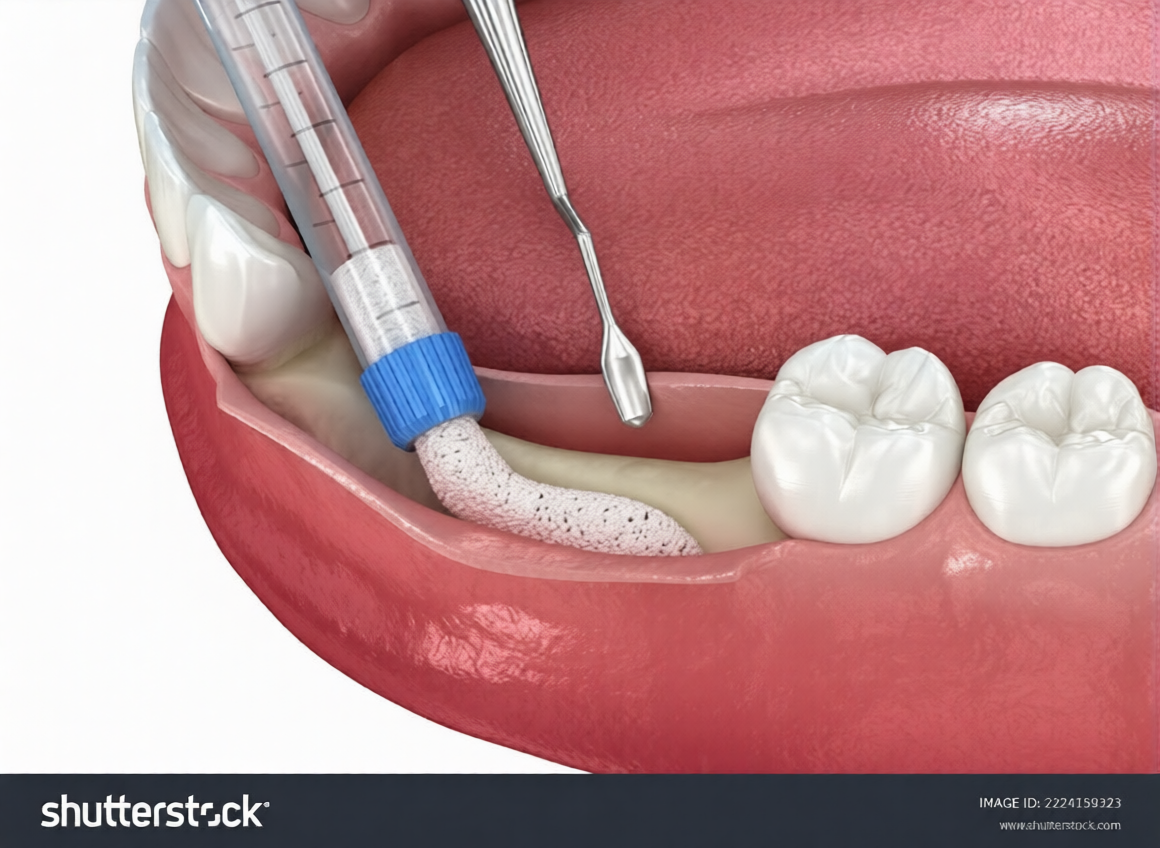

Bone grafting rebuilds lost jawbone, usually preparing for dental implants. When teeth are missing for extended periods, the bone beneath them deteriorates. Implants require adequate bone for stability.

During the procedure, we place grafting material into the area where bone has been lost. This material serves as a scaffold, encouraging your body to generate new bone. Over several months, your natural bone grows into and around the graft material, creating a stable foundation for implants.

Types of grafting material include your own bone from another area of your mouth, processed bone from donors, or synthetic materials. Each has advantages depending on the specific situation.